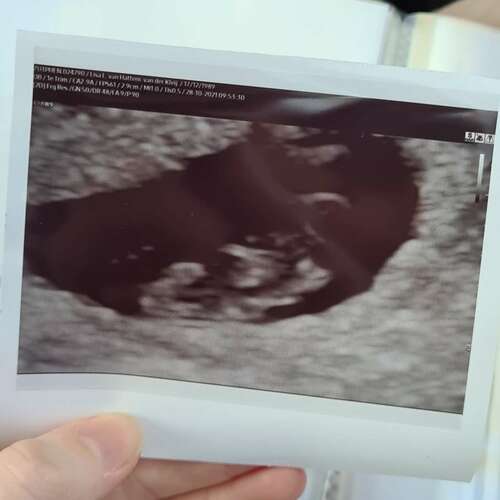

Het hangt denk ik ook van de kwaliteit van de echo apparatuur af. Mij was de eerste echo bij de gynaecoloog, dat was gewoon een pixelig bolletje. Latere echo bij het echoscopie centrum zie je veel meer. Waarschijnlijk heb jij gewoon een goed echo apparaat getroffen, waardoor je al veel meer vorm kon zien.